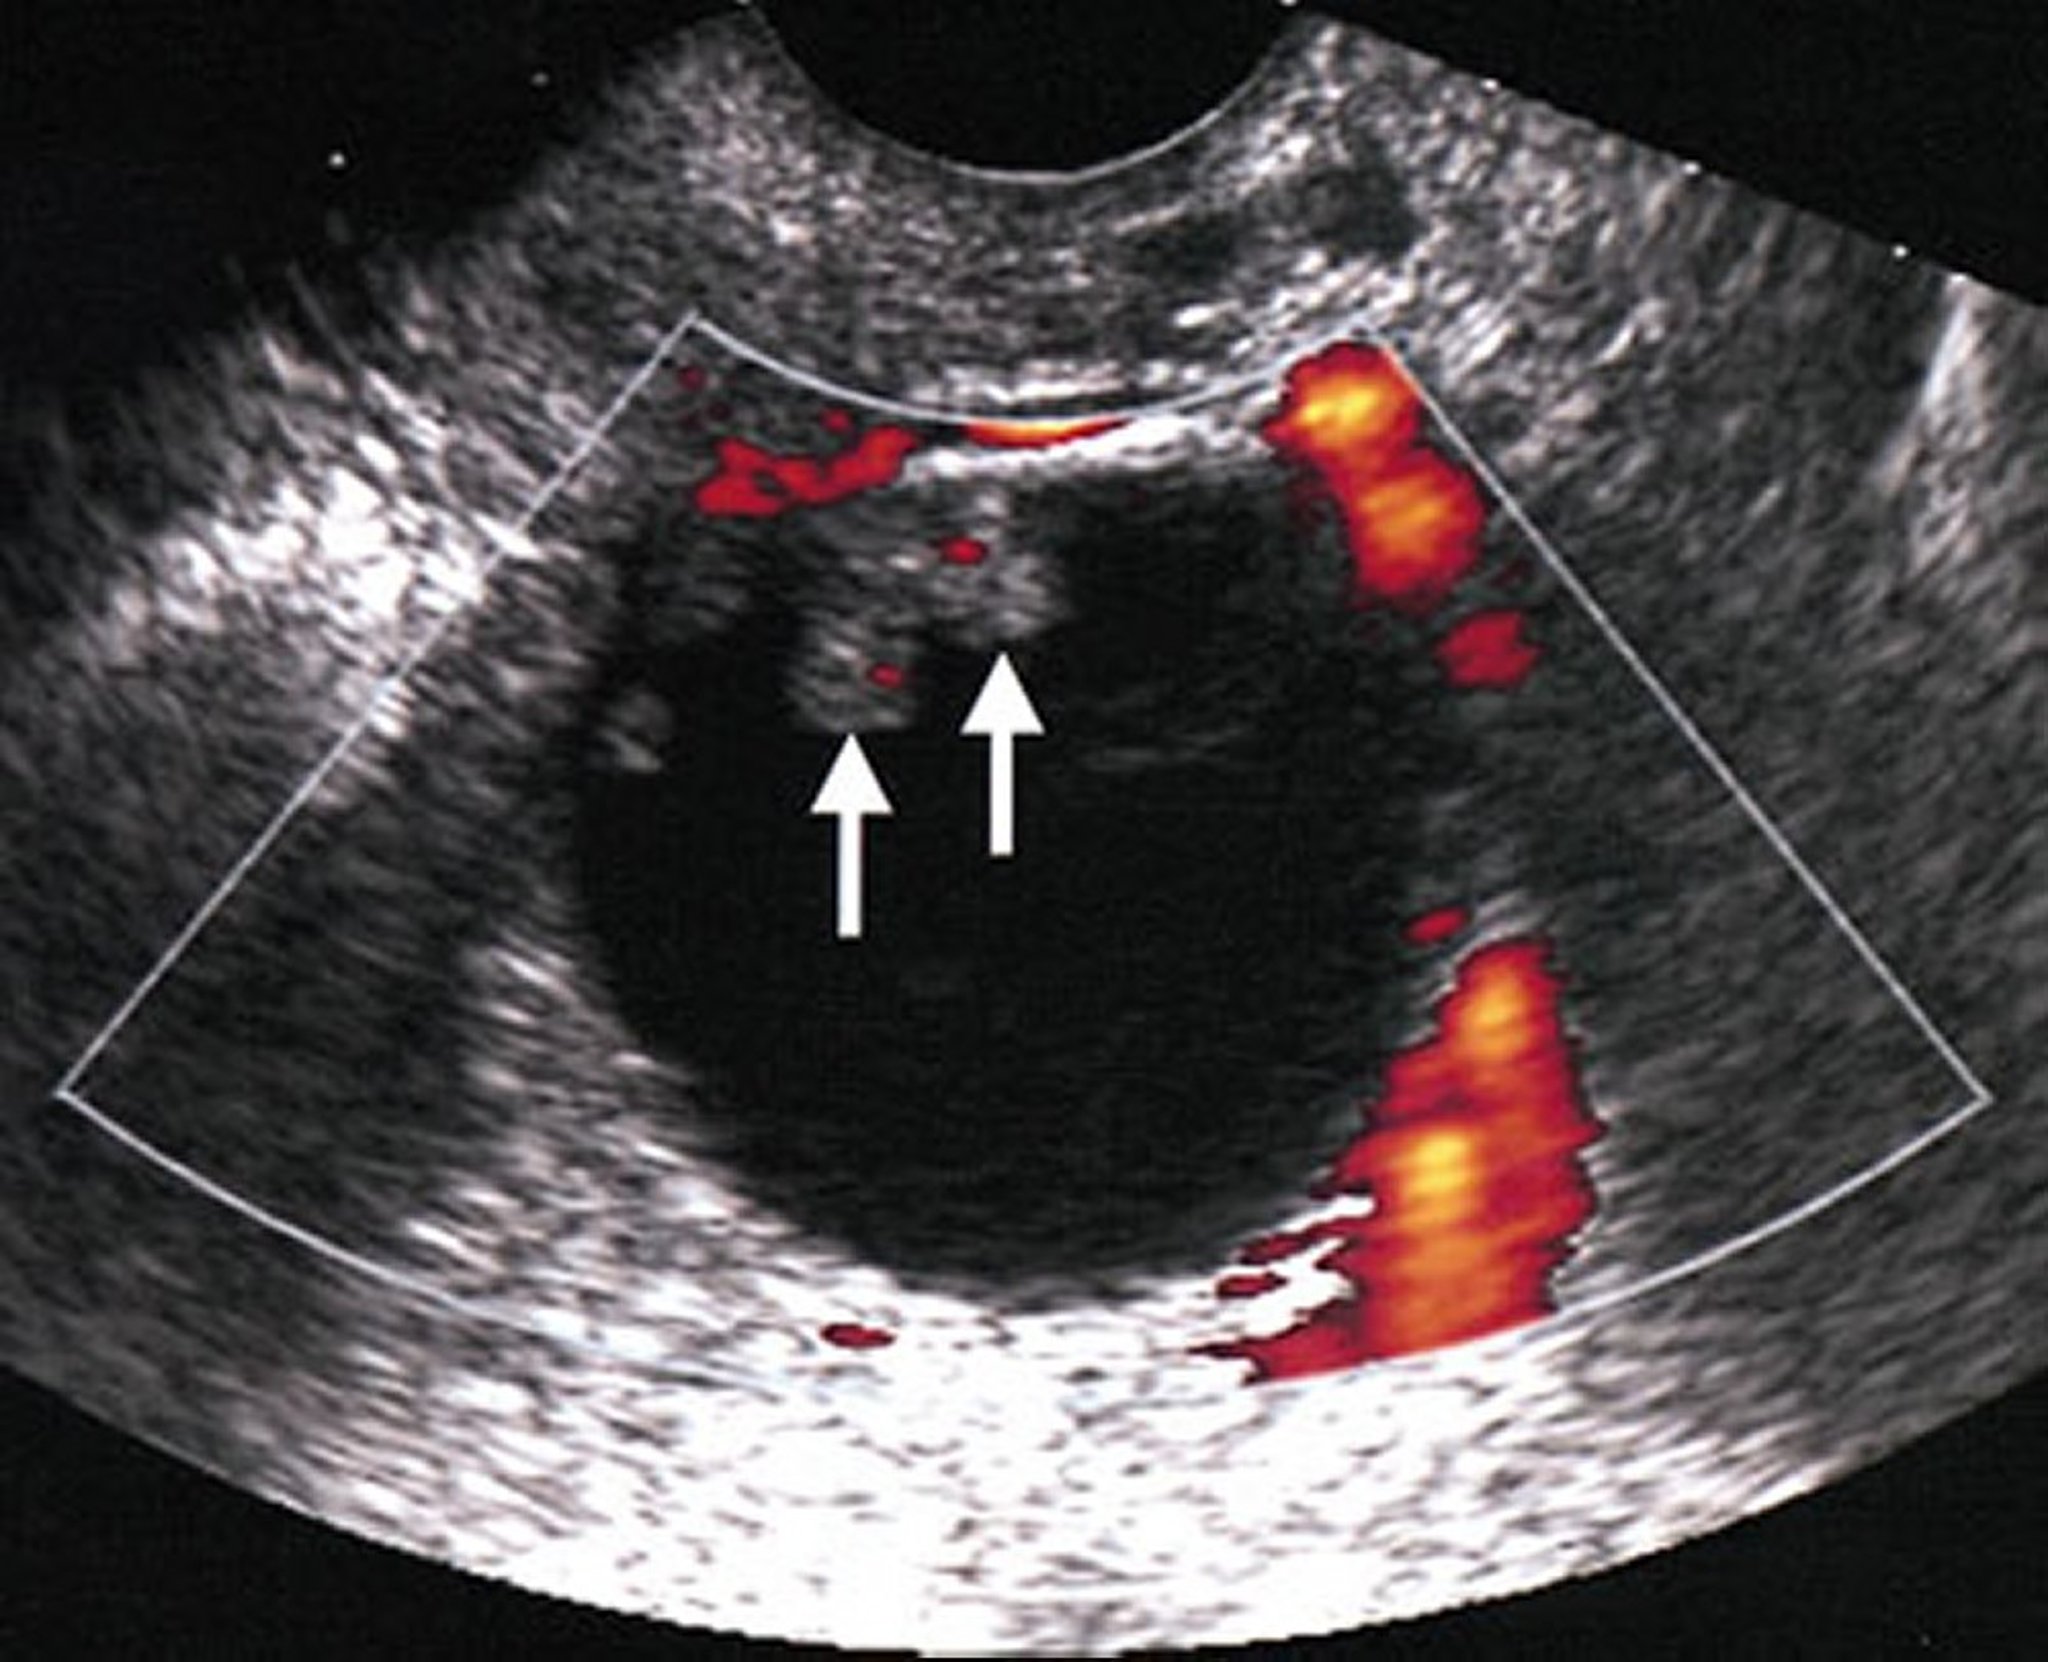

Ultrasound of a Malignant Ovarian Mass

In this ovarian mass, malignancy is suggested by the presence of echogenic solid components (indicated by arrows) within an otherwise anechoic cystic mass. A Doppler study shows flow within these solid components, confirming that they represent solid malignant components.

By permission of the publisher. From Hricak H, Coakley F, Bergman A. In Atlas of Cancer. Edited by M Markman, RR Barakat, and WJ Hoskins. Philadelphia, Current Medicine, 2002.